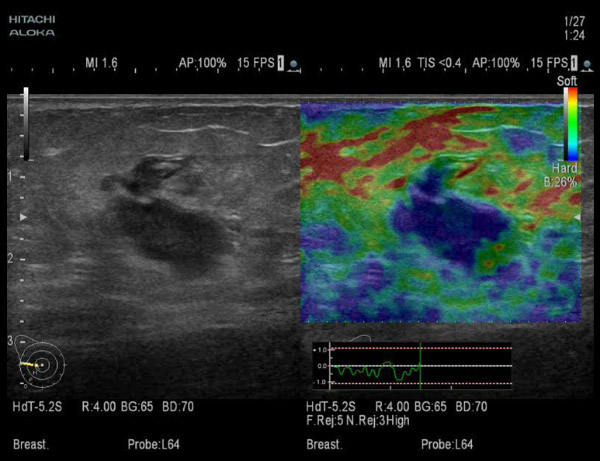

Эластография щитовидной железы в Могилеве

В учреждении здравоохранения «Могилевская поликлиника №6» эластография щитовидной железы выполняется на новых ультразвуковых аппаратах экспертного класса Hitachi Arietta S70, Mindray DC-80 и Mindray...